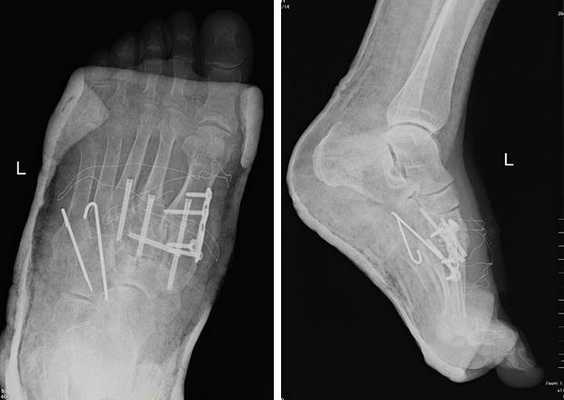

При смещении более 2 мм, нестабильности при функциональных тестах - рекомендовано открытое устранение вывиха с жёсткой фиксацией винтами или пластинами. Используются один или два продольных доступа в 1 и 2 межплюсневых промежутках. После обнажения первого предплюсне-плюсневого сустава первым этапом устраняется межклиновидная нестабильность, вторым этапом устраняется предплюсне-плюсневая нестабильность. В послеоперационном периоде сразу начинается разработка активного объёма движений. Нагрузку на стопу начинают постепенно, с тем чтобы полностью её восстановить к 6-8 неделе. Удаление спиц Киршнера производится через 6-8 недель, компрессирующих винтов через 3-6 месяцев. Возвращение к полной физической активности не ранее 9-12 месяцев после операции.

Открытое вправление вывиха, трансартикулярная фиксация 1-2-3 предплюсне-плюсневых суставов винтами.

После осмотра в отделении ортопедии №2 ГКБ №13 принято решение о проведении операции - открытому устранению вывиха, артродезе 1-2-3 плюсне-клиновидных суставов, 1 межклиновидного сустава при помощи винтов и пластины, трансартикулярной фиксации спицами 4-5 плюсне-клиновидных суставов.

Вершиной, ключом, блокирующим клином - в общем главной частью сустава Лисфранка является 2 плюсне-клиновидный сустав. По этой причине мы предпочитаем начинать фиксацию именно с него. Для артродеза используем винты с направленной в разные стороны резьбой FT Arthrex диаметром 4 мм. Они позволяют создать мощную межфрагментарную компрессию, а за счёт глубокой резьбы очень надёжно фиксируются в кости.

После восстановления 2 луча выполняем артродез межклиновидного сустава и 1 плюсне-клиновидного сустава. Учитывая что основная нагрузка ложится на 1 луч, дополнительно стабилизируем его при помощи пластины.